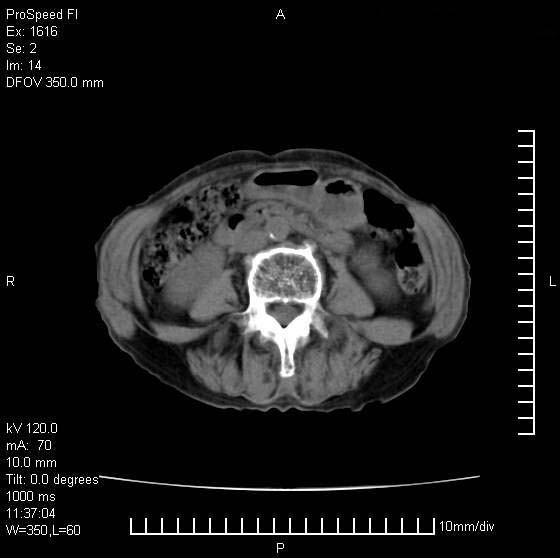

患者无明显临床症状,肝左叶发现一个圆形密度不均的低密度灶,边界较清楚,大小37x45mm,ct值35-70,患者犹豫做增强,如有增强片,我再发上,现先请各位老师会诊.

左肝外叶可见较大圆形低密度影,病灶可见较光整清晰边界,病灶内可见多量条状稍高密度影,右肝前叶亦可见圆形结节状低密度影,边界清晰,密度均匀,考虑1肝多发囊肿,左肝囊肿内出血2肝包虫病3左巨块型肝癌出血合并右肝转移或合并右肝囊肿

左肝外叶可见较大圆形低密度影,病灶可见较光整清晰边界,病灶内可见多量条状稍高密度影

考虑:肝包虫病

肝左叶类圆形低密度影,内可见略高密度影,边界清晰周边可见环形低密度带,考虑肝腺瘤可能,建议增强扫描除外肝血管瘤与肝癌

肝左叶不均匀占位,内有斑片状高密度出血灶,内侧缘似有假包膜,腹主动脉周围及肝门区结构紊乱,似有增大淋巴结,考虑:肝左叶hcc并淋巴结转移。建议增强扫描除外其他。